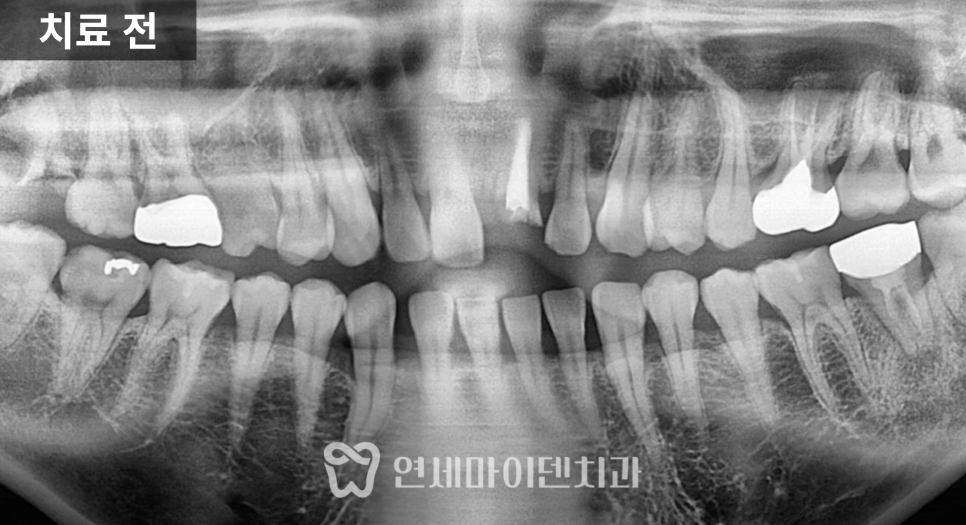

이번 환자분은 고령의 환자분이었습니다.

왼쪽 어금니가 빠진 뒤 장기간 방치되었고,

남아 있던 치아는

쓰러지고 흔들리는 상태였습니다.

치료 전 방사선 사진을 보면

치아가 쓰러진 문제도 있었지만

무엇보다 뼈의 폭과 높이가

많이 줄어든 상태

였습니다.

잇몸도 전반적으로 약했고,

1차 수술: 발치, 염증 정리, 식립과 이식 동시 진행

첫 단계에서는

아래 1개, 위 2개

3개의 임플란트를 계획했습니다.

위쪽은 상악동이 내려와 있어

상악동 거상술과 뼈이식을 함께 시행한 뒤

그 공간에 임플란트를 식립했습니다.

아래쪽은 뼈 상태가 비교적 유지되어 있었지만

안정적인 고정을 위해

필요한 부위에 뼈이식을 병행했습니다.